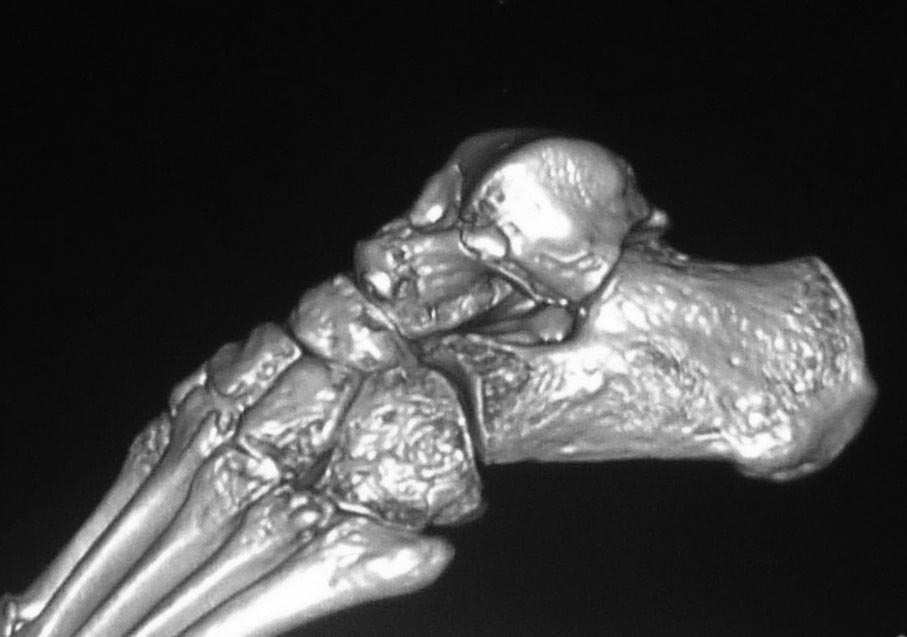

Вероятнее всего, речь изначально шла о не устраненном во время операции

вывихе проксимального фрагмента таранной кости. Во вложении похожий

случай, оперированный 10 дней назад (с послеоперационными снимками). Для

сравнения стрелками на двух рентгенограммах показан нависающий над

пяточной костью вывихнутый фрагмент таранной кости. На компьютерной

томограмме видно гораздо лучше. Так что о живом подтаранном суставе при